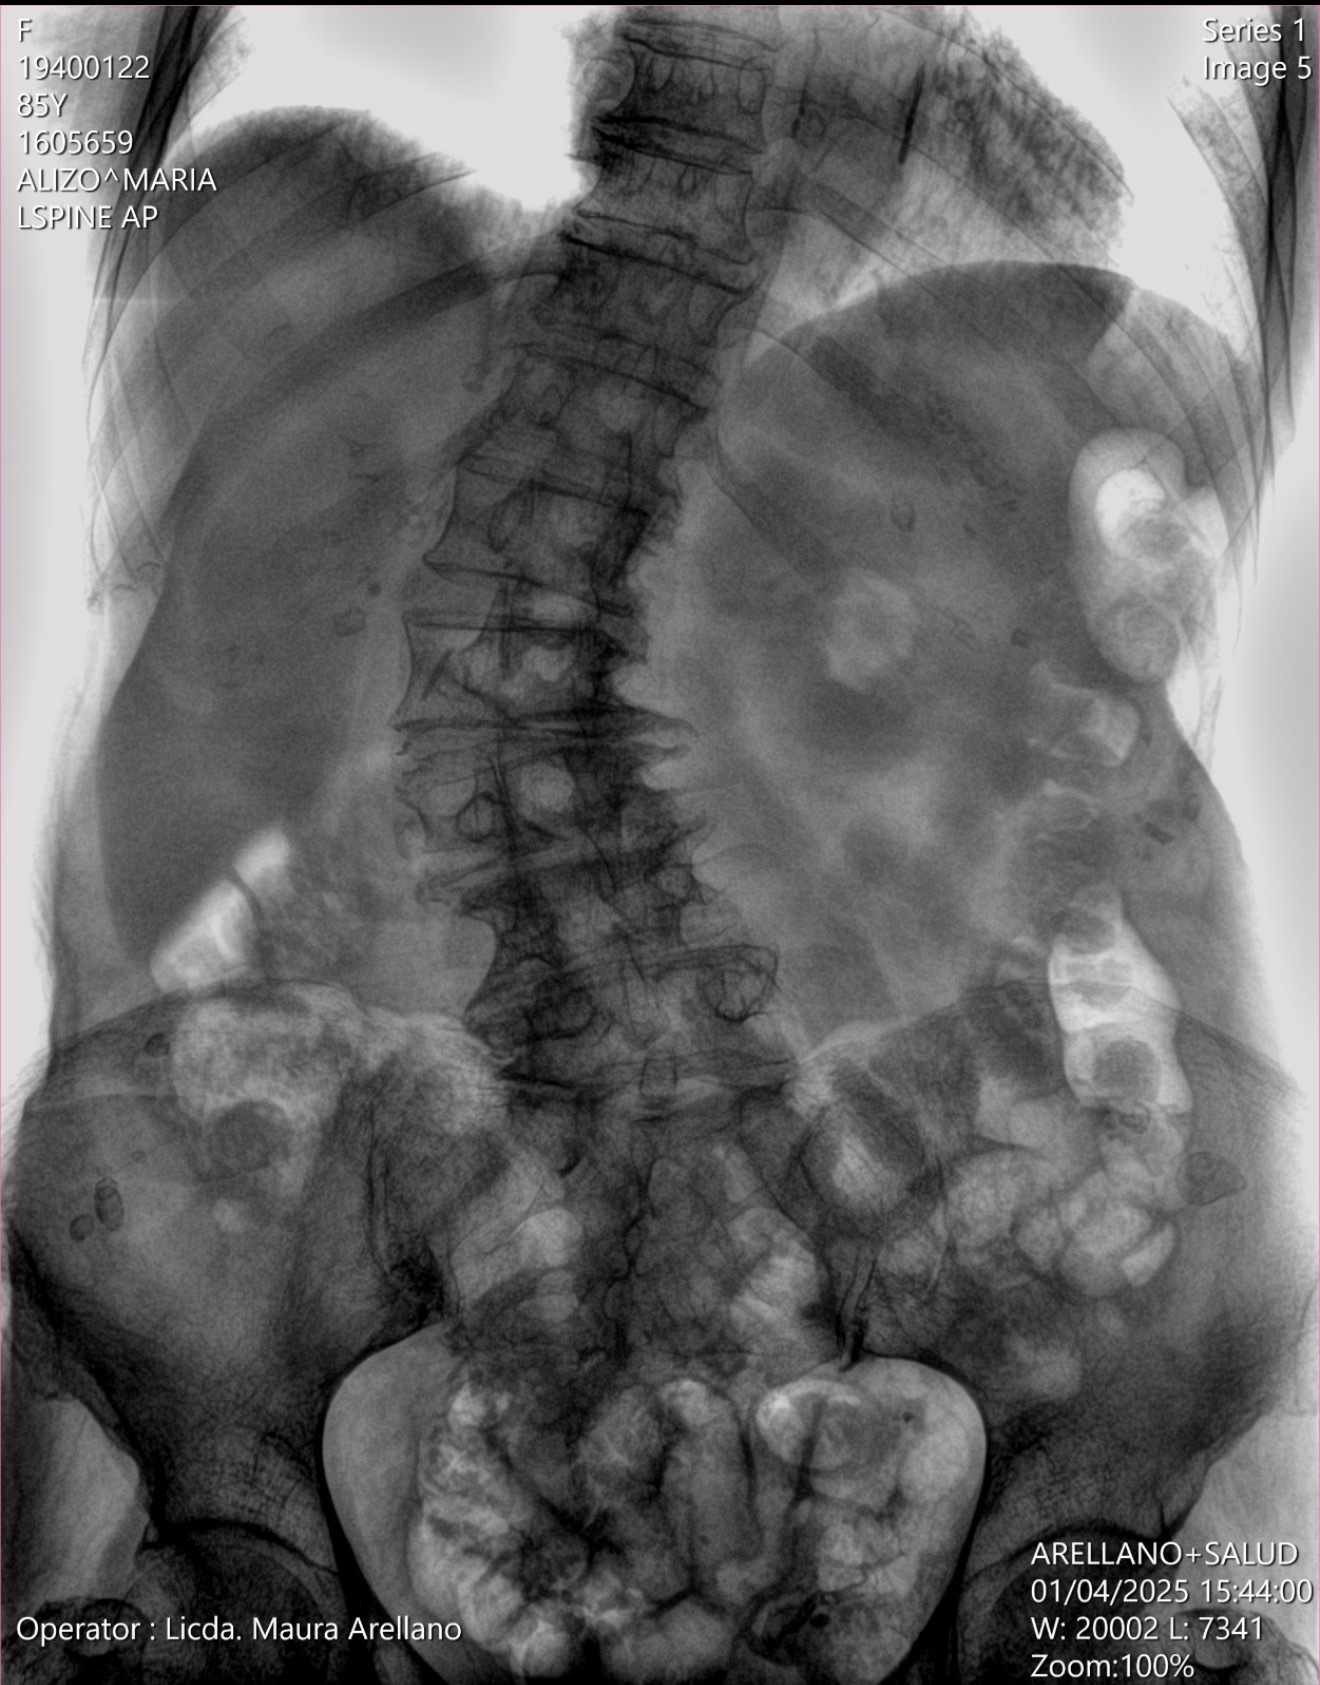

Durante varios años, ha sufrido de dolor crónico en la parte baja de la espalda, de intensidad moderada a severa. El dolor ahora se irradia hacia su pierna derecha y ha empeorado progresivamente. También está experimentando debilidad muscular en la pierna derecha, así como entumecimiento y hormigueo en ambas piernas. En los últimos seis meses, su condición ha empeorado significativamente a pesar del tratamiento médico.

Después de una evaluación médica y estudios de imagen, sus médicos han determinado que la cirugía es ahora necesaria. Sin este procedimiento, su movilidad y calidad de vida continuarán deteriorándose.